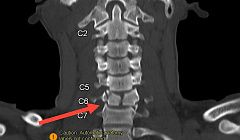

В Бурятии подросток стал инвалидом после неудачного ныряния

Юноша сломал шею.